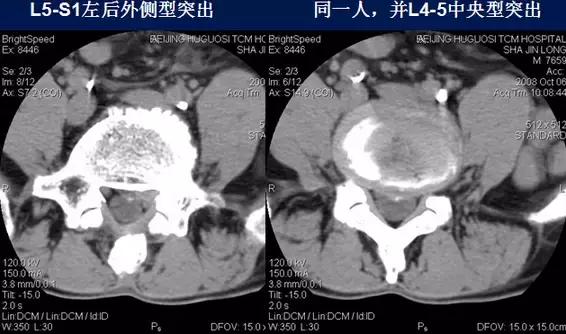

⑶后外侧型:椎间盘影于椎间孔方向局限性超出椎体边缘,神经根受压,椎间孔、侧隐窝变窄。

⑴中央型:椎间盘影局限性超出椎体边缘,硬膜囊可受压,硬膜外脂肪间隙变窄、消失,可伴纤维环钙化。